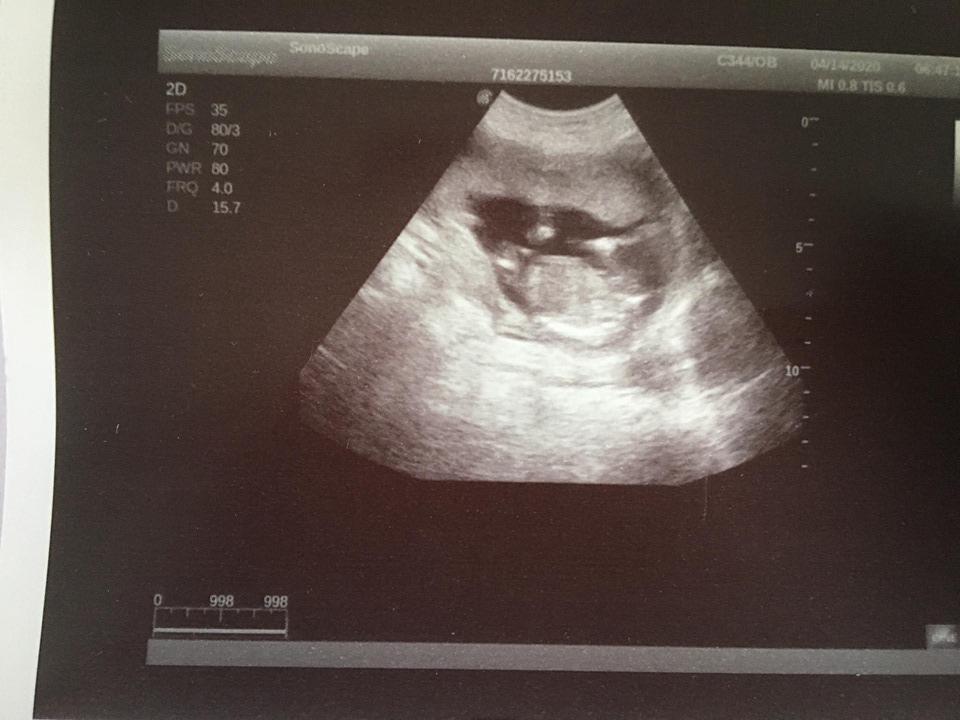

Je to holčička nebo chlapeček? Foto ultrazvuku

@lilian2111 já se v těch hrbolcích vůbec,ale vůbec nevyznám hah 😀 😀 ale pamatuji si u kluků,že ten pinďour šel vidět jasněji na těch prvních screeningách než teď u malého Damiánka či Dominička 😀 😀

@juliemichal škoda, že ta fotka je rozmazana. Ale vypadá to spíš na kluka, opravdu tam něco trčí, ale na tento týden by to byl tedy už poradny chlapak 😃 až půjdete v tom 15+4, poproste o fotku pohlaví ze spodu, to už by mělo být pohlaví poznat.

@kajda3 no to je fakt na 12+1 by to byl pořádný chlapák hah,takže to co tam trčí to určitě nebude šula 😀 😀 ale uvidíme ♥ ♥ určitě v úterý poprosím dr aby mi dala fotečku pohlaví ♥ ♥

@sebinka123 kéž by ta první fotka (screening) podle dr to vypadá na kluka,druhá fotka 2 dny později u mého gynekologa ten mi řekl,že mezi nožičky nic nevidí,že by ho zajímalo kde doktor viděl chlapečka 😀 😀 ale,že z největší pravděpodobností mi pohlaví řekne až ve 20tt

@juliemichal to jsem na tebe zvedava! 😁 musíš nám dat v úterý hnedka vědět. První fotka bych řekla na 99% kluk, ale ta druha zase vypadá na holčičku. Moc bych ti tu holčičku prala 🙂

jinak koukej první foto 14+5 tj dnes,druhé foto 14+1 třetí těhotenství s Mateem 😀 😀 a mám ty břicha úplně jiné u kluků jsem měla úplně stejné jako u Matea a teď fakt úplně jiné 😀 😀

@eiram7 jasná holčička, gratuluji 💃ve 13. týdnu je to jisté tak na 95 % 😊 navíc k tomu tento snímek hrbolek ukazuje pěkně 👍